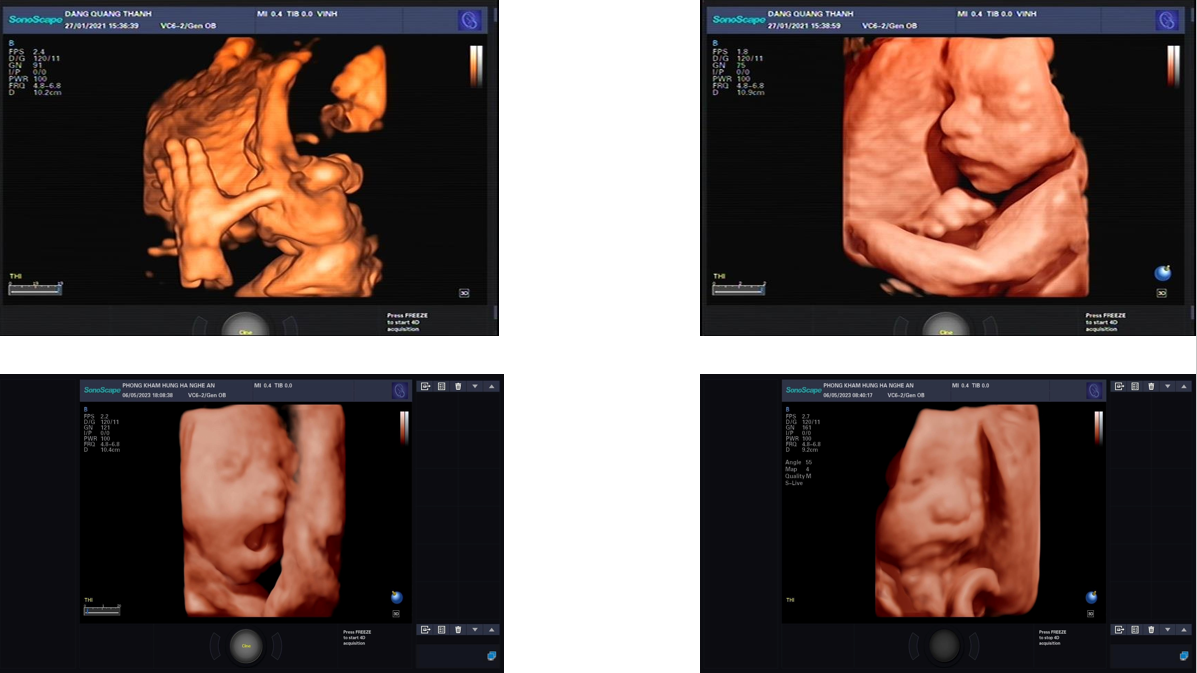

- Máy siêu âm 5D SonoScape P25 với S-live real time: bác sĩ vừa khám, vừa sử dụng chế độ S-live làm mịn và nét hình ảnh, không cần dừng lại để sử dụng như trước.

- Chế độ auto-face: tự động bắt hình ảnh khuân mặt em bé

- Đầu dò âm đạo 4D: ngoài khám các bệnh phụ khoa, có thể phát hiện thai sớm, mang thai ngoài tử cung

Hình ảnh thực tế trên máy siêu âm 5D SonoScape P25